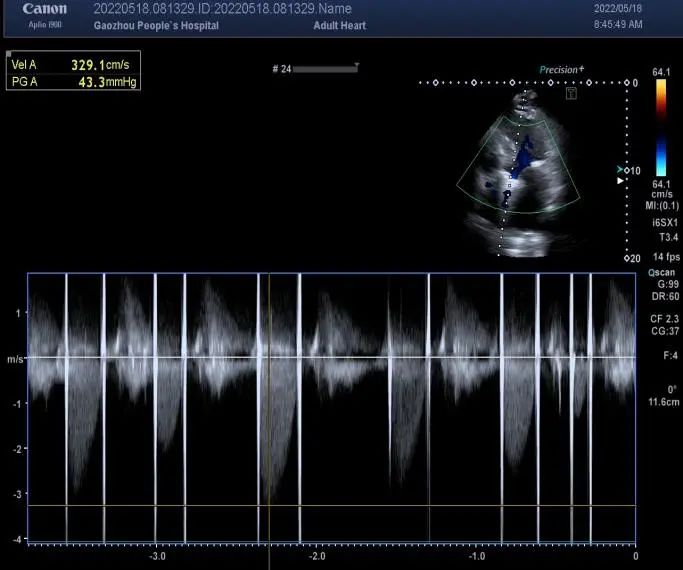

日前,高州市人民医院心血管外科曹勇教授团队为一名71岁换瓣术后27年机械瓣膜功能障碍的女性患者成功实施了双瓣膜瓣环扩大重建+瓣膜替换手术,该手术又称为Commando手术或UFO手术。该患者27年前在高州市人民医院心外科行主动脉瓣机械瓣置换手术,术中使用国产G-K瓣。术后康复出院,长期服用华法林抗凝治疗。1个月前出现气促、腹胀、下肢肿胀,复查心脏彩超提示主动脉瓣流速增高3.3m/s,压差43.56mmHg,二尖瓣、三尖瓣中重度关闭不全,合并严重心衰,有手术的指征,为进一步手术治疗入住高州市人民医院心血管外科一区(见术前心脏彩超图)。